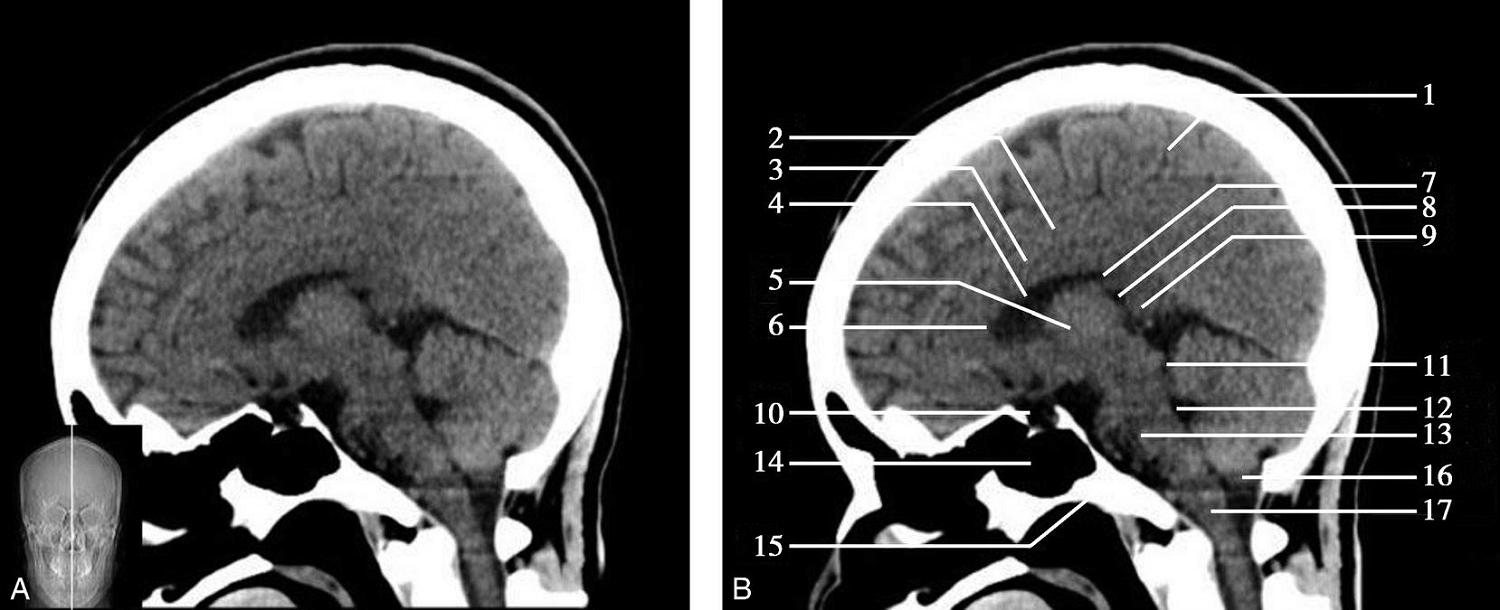

重要结构:胼胝体、垂体、中脑导水管、扣带回、中央沟、第三脑室、斜坡(图1-2-59、图1-2-60)。

图1-2-59 正中矢状面CT

A.矢状面;B.矢状面标注

1.中央沟;2.扣带回;3.胼胝体体部;4.侧脑室;5.中脑;6.胼胝体膝部;7.穹隆;8.第三脑室;9.胼胝体压部;10.垂体;11.中脑导水管;12.第四脑室;13.脑桥;14.蝶窦;15.斜坡;16.小脑扁桃体;17.延髓

图1-2-60 正中矢状面骨窗CT

1.顶骨;2.枕骨;3.斜坡;4.额骨;5.蝶鞍

此层面可显示胼胝体全貌,它位于层面中央区域,是呈上凸下凹的弧形结构,由前向后分为嘴、膝、体和压四部分。扣带回环绕胼胝体上方,扣带沟位于扣带回的上方。大脑半球中部和后部分别可见较深且恒定的中央沟和顶枕沟。中央沟为是额叶顶叶分界标志。

胼胝体下方为侧脑室及穹窿,第三脑室借穹窿与前上方的侧脑室体部分开,背侧丘脑的内侧面以及中脑顶盖分别为第三脑室的外侧壁和底。第三脑室向前籍室间孔与侧脑室相通,向下经中脑导水管通第四脑室。中脑腔狭窄呈管状,即称为中脑导水管,中脑导水管畸形,常见者为导水管的分叉畸形和狭窄,其次可见中脑导水管膈膜,造成先天性脑积水。

脑干由中脑、脑桥和延髓组成,自第三脑室底向下后稍斜行,移行于颈髓。由上至下,脑干腹侧可见脚间池、桥前池和延髓池,脑干背侧可见大脑大静脉池、四叠体池和小脑延髓池。

垂体位于蝶鞍内,其前部为腺垂体,后上部分为神经垂体。垂体下方为鞍底及蝶窦,上缘因鞍膈存在而平直,垂体借垂体柄向上连于丘脑下部。垂体的前上方见视交叉和视束。斜坡作为前颅窝底的重要组成部分与多个重要结构相比邻,矢状位呈三角形,颅内肿瘤或颅外鼻咽部恶性肿瘤均可侵犯至此,原发肿瘤常见为脊索瘤。小脑幕居枕叶和小脑之间,向后下连接窦汇,向前至中脑后方游离,称小脑幕切迹。小脑幕下方为小脑扁桃体。成年人小脑扁桃体下缘由枕骨大孔向下疝入椎管超过5mm称为Chiari畸形,以矢状位显示最佳。